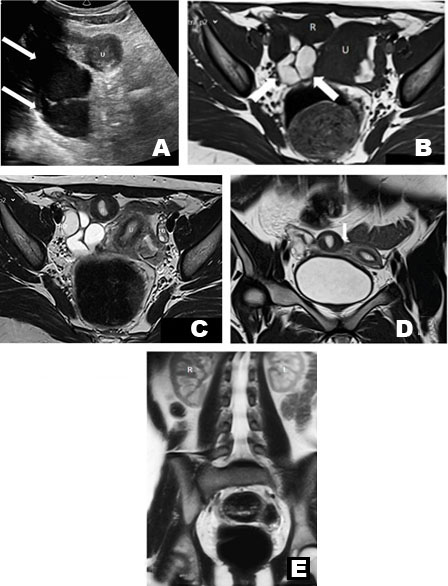

The appendix was normal on transabdominal US, but there was a tubular hypoechoic structure measuring 7.5 cm L × 5.5 cm AP × 4.0 cm W with low level internal echoes and absent color flow on Doppler interrogation. The right ovary was not sonographically identified. Diagnostic laparoscopy performed due to clinical suspicion of right ovarian torsion revealed a right hematosalpinx arising from a non-communicating right rudimentary horn in a unicornuate uterus and normal ovaries. Subsequent hysteroscopy showed a single cervix leading to the main left uterine horn.

Pelvic MRI performed one month later confirmed the non-communicating right cavitary horn, the main left horn with a normal cervix, and a right hematosalpinx showing bright signal intensity with dependent low T2 signal representing retracted clot. The ovaries were normal (Figure 1). The patient underwent an elective right hemi-hysterectomy with ipsilateral salpingectomy.

Figure 1: 12-year-old female with cavitary rudimentary horn in a unicornuate uterus presenting at menarche. (A) Transverse transabdominal US showed a tubular right adnexal structure containing low level echoes (white arrows) and through transmission. Uterus (U). (B) T1 weighted axial spin echo image (TR:412 TE:12 ms) shows a right hematosalpinx (white arrows) with bright signal bloody contents from retrograde menstruation. Main uterine body (U). Rudimentary horn (R). (C) T2 weighted axial pelvic MRI (Turbo Spin Echo TR:3040 TE 94 ms, 3 mm skip 3.6 slice thickness) shows uterine zonal anatomy within the main and rudimentary horns. Right ovary (RO). Left ovary (LO). (D) T2 weighted coronal MRI (TR:3140 TE:84 ms, 3 mm skip 3.6 slice thickness) demonstrates the contiguity (white arrow) of rudimentary horn (R) with the main uterine body (U). (E) Coronal Scout Haste scan (TR:900 TE:93 ms) shows normotopic kidneys. (Right kidney—R, Left kidney—L).